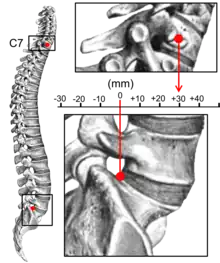

Sagittal balance measurement[15]

Kyphosis can be graded in severity by the Cobb angle. Also, sagittal balance can be measured. The sagittal balance is the horizontal distance between the center of C7 and the superior-posterior border of the endplate of S1 on a lateral radiograph.[15]